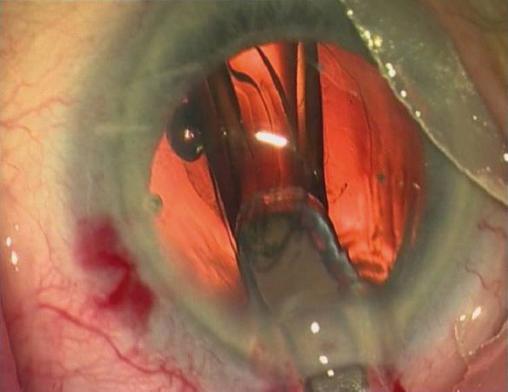

Le traitement de la cataracte est uniquement chirurgical, le plus souvent par extraction extracapsulaire du cristallin par phakoémulsification avec mise en place d’un implant intraoculaire. Il peut être réalisé sous anesthésie topique, locale ou générale et en ambulatoire. Voir : Arné JL. Cataracte. Rev Prat 2010;60:1281-6.